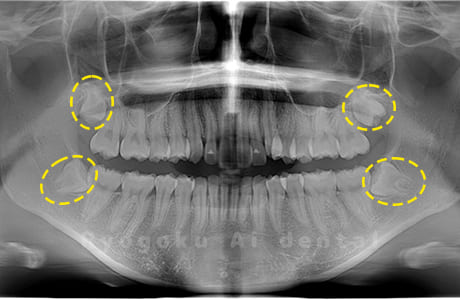

Case03

- 原因

- 上顎、下顎の親知らず

- 治療内容

- 上下4本の親知らずを抜歯したケースです。

<リスク・副作用>

手術後は痛み、腫れ、痺れなどの副作用が生じる場合があります。